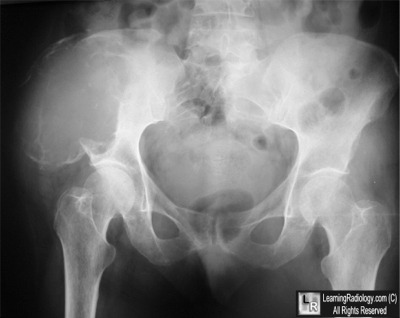

Frontal Radiograph of the Pelvis

- 61 year-old female with pain in the right side. What's the most likely primary malignancy?

3. Renal Cell Carcinoma

Renal Cell Carcinoma

- Metastases are most common

malignant bone tumors

- Most involve axial skeleton

- Skull, spine and pelvis

- Rarely do mets occur distal to

elbows or knees

- Spread hematogenously

- Most frequently occur where

red bone marrow is found

- Mets to spine frequently destroy

posterior vertebral body including

pedicle first=”pedicle-sign”